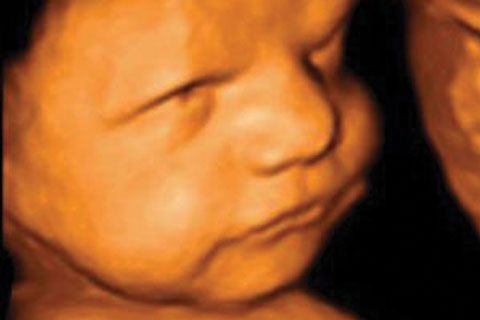

La  tecnología ofrece ver hoy a nuestro bebé dentro del útero mediante aparatos de ecografía que procesan la imagen en tres dimensiones y una cuarta dimensión que es el tiempo, lo que será eco tridimensional en tiempo real. Esta ecografía no tiene como finalidad el diagnostico de malformaciones sino que se usa para fines meramente emocionales.

En los inicios de las semana 24 pueden comenzar a realizarse las ecografías tridimensionales, en estas no siempre se consigue la visualización, digamos «bonita» debido a la posición del feto.